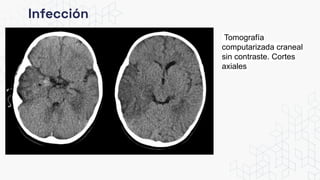

Infección

Tomografía

computarizada craneal

sin contraste. Cortes

axiales